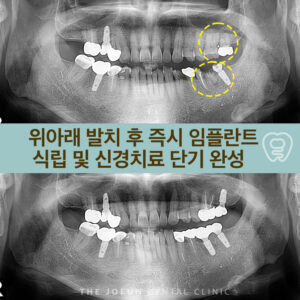

달서구임플란트잘하는곳 치조정 접근법을 통한 상악동 뼈이식술 임플란트는 치아가 빠진 부위에 티타늄으로 만들어진 인공치근을 치조골에 식립하여 상부에는 크라운을 제적하여 연결하는 보철치료르 말합니다. 치아의 뿌리부터 머리까지 자연치와 비슷한 모양으로 심미성이 뛰어나고, 자연치와 유사한 기능을 보이는데요. 이는 잇몸뼈에 식립체를 직접 식립하게 되는데 진행을 위해서는 치조골의 양과 상태가 충분해야 합니다. 치아를 상실했어도 치조골 상태가 더보기…